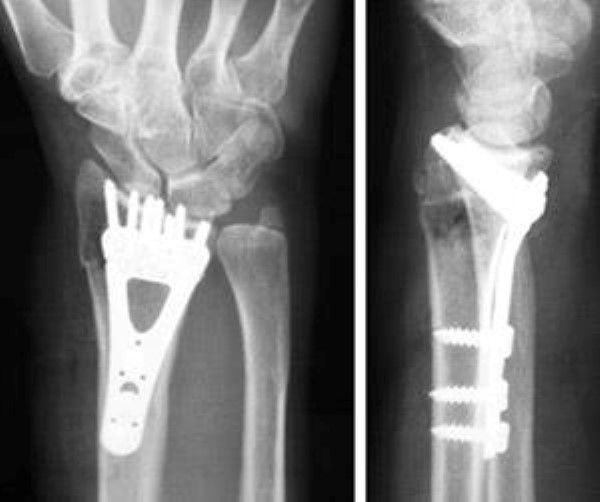

42+ Broken Wrist Bones Xray US. The game uses a camera for a more realistic effect! It's important to treat a broken wrist as soon as possible.

Broken bones include arm, wrist, leg, ankle, foot, rib, back, skull and more.